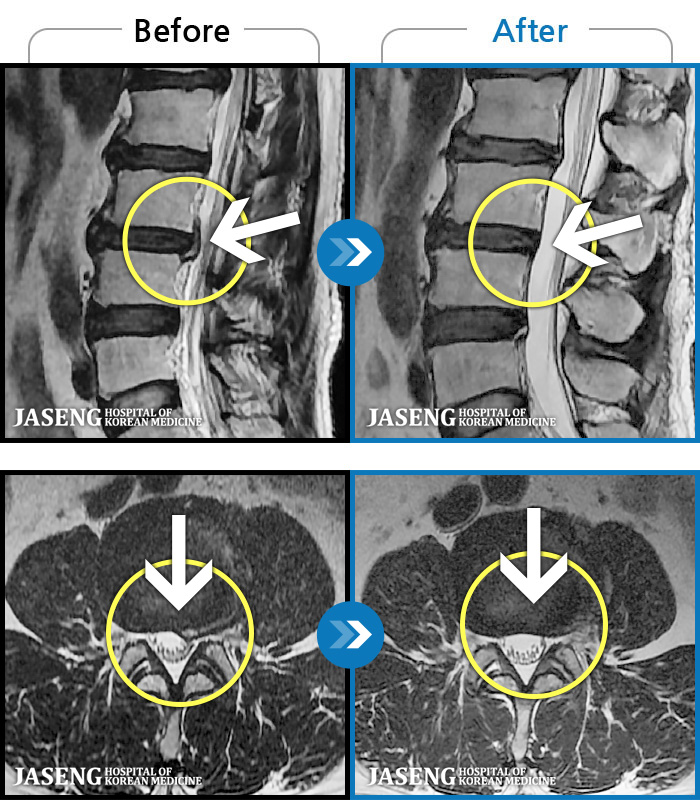

허리디스크

도움받은 사례

해운대 · 김상돈 원장

하지 저림과 통증이 개선되어서 일상생활이 너무 즐겁습니다.

촬영시기

2023.09.18 ~ 2025.01.27

2025.02.05